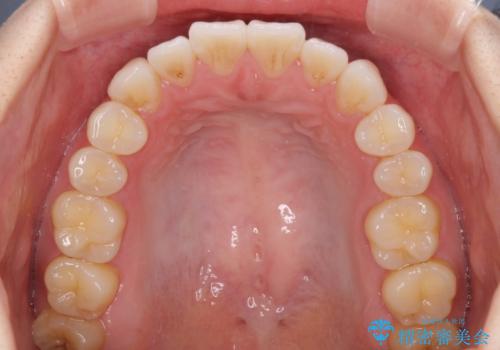

- 矯正治療の後戻りを気にして来院された患者様です。

後戻りは軽微でしたが、舌突出癖が認められ、初診時には上下前歯に舌がはまるスペースができていました。

舌突出癖の改善を行いながら、インビザライン・ライトにより矯正治療を行うこととしました。

舌突出癖の改善により上下前歯が接触するようになり、前歯でものを咬みきる必要のある食事がスムーズに行えるようになりました。